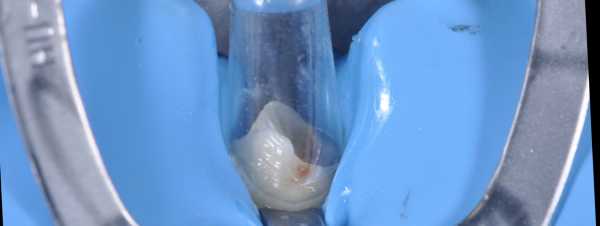

Luxacore Z

Luxacore Z – это универсальный композиционный материал двойного отверждения, предназначенный для установки стекловолоконных штифтов и восстановления культи зуба при наличии глубокой полости. Важно помнить о том, что перед световым отверждением нужно подождать две минуты до завершения процесса химического отверждения.

(Рис.6)

Восстановление культи зуба

Одновременно с внесением в корневой канал материала Luxacore Z, проводится восстановление культи зуба. Для этого core-форма заполняется тем же материалом и устанавливается на зуб. Внутри формы создается давление, которое необходимо для сохранения однородности материала всей реставрации.

(Рис.7)